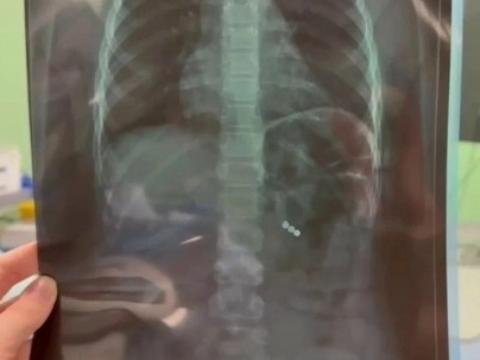

В Областной детской клинической больнице Иркутска врачи провели срочную операцию восьмилетней школьнице, которая во время игры случайно проглотила три неодимовых магнитных шарика. Благодаря быстрой реакции медиков ребёнка удалось спасти.

Главный врач ИОДКБ Юрий Козлов сообщил в своём телеграм-канале, что попавшие в организм магниты притянулись друг к другу и пробили кишечные стенки. По его словам, хирурги выполнили малоинвазивную операцию и оперативно извлекли опасные предметы. Девочка уже идёт на поправку.